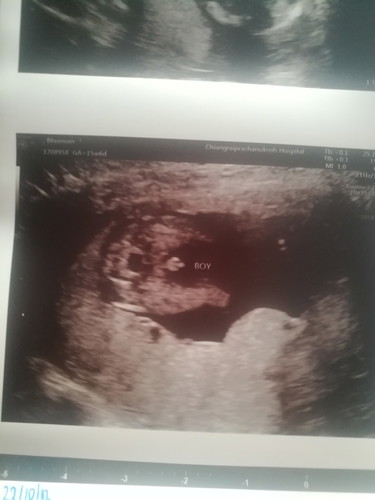

แม่ๆคะวันนี้เราไปซาวด์มาหมอบอกได้ลูกชาย ความแม่นยำอยู่ที่99% ตอนคลอดมีโอกาสที่ลูกจะเกิดเป็นหญิงไหมคะ ตอนนี้ตั้งครรภ์16สัปดาห์ค่ะ

เห็นจู๋ชัดมากเลยค่ะ 😄 ถ้าเป็นผญจะเรียบๆค่ะ